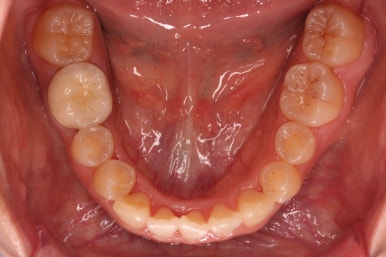

문제의 시작은 바로 아래 앞니였어요.

맨 아래 오른쪽 사진에 화살표를 보시면 앞니가 4개여야 하는데 3개 밖에 없네요.

아래 앞니 3개인 채로 마무리를 하기도 하고 4개처럼 보이게끔 마무리를 하기도 합니다.

이번 환자분의 경우는 치아 크기와 비율, 교합 등을 전반적으로 고려해서 아래 앞니가 마치 4개인 것처럼 마무리를 하기로 했습니다.

뒤쪽 치아를 차례차례 끌고 당겨와서 앞니를 대신하는거죠.

물론 기간은 많이 걸리나 현재로서는 가장 합리적인 방법으로 판단했습니다.

이제는 아래 앞니가 3개이기 때문에 생기는 중앙선의 문제, 치아 갯수의 문제를 맞춰나가기로 했습니다.

계획은 오른쪽 아래 송곳니 ~ 어금니 모든 치열을 앞쪽으로 밀어줘 아래 앞니를 마치 4개인 것처럼 만드는 것입니다.

위쪽은 미니스크류 위치를 바꿔줘 교합을 맞춰주고요.

아래쪽은 마찬가지로 미니스크류를 비대칭으로 식립해서 어금니를 당겨줍니다.